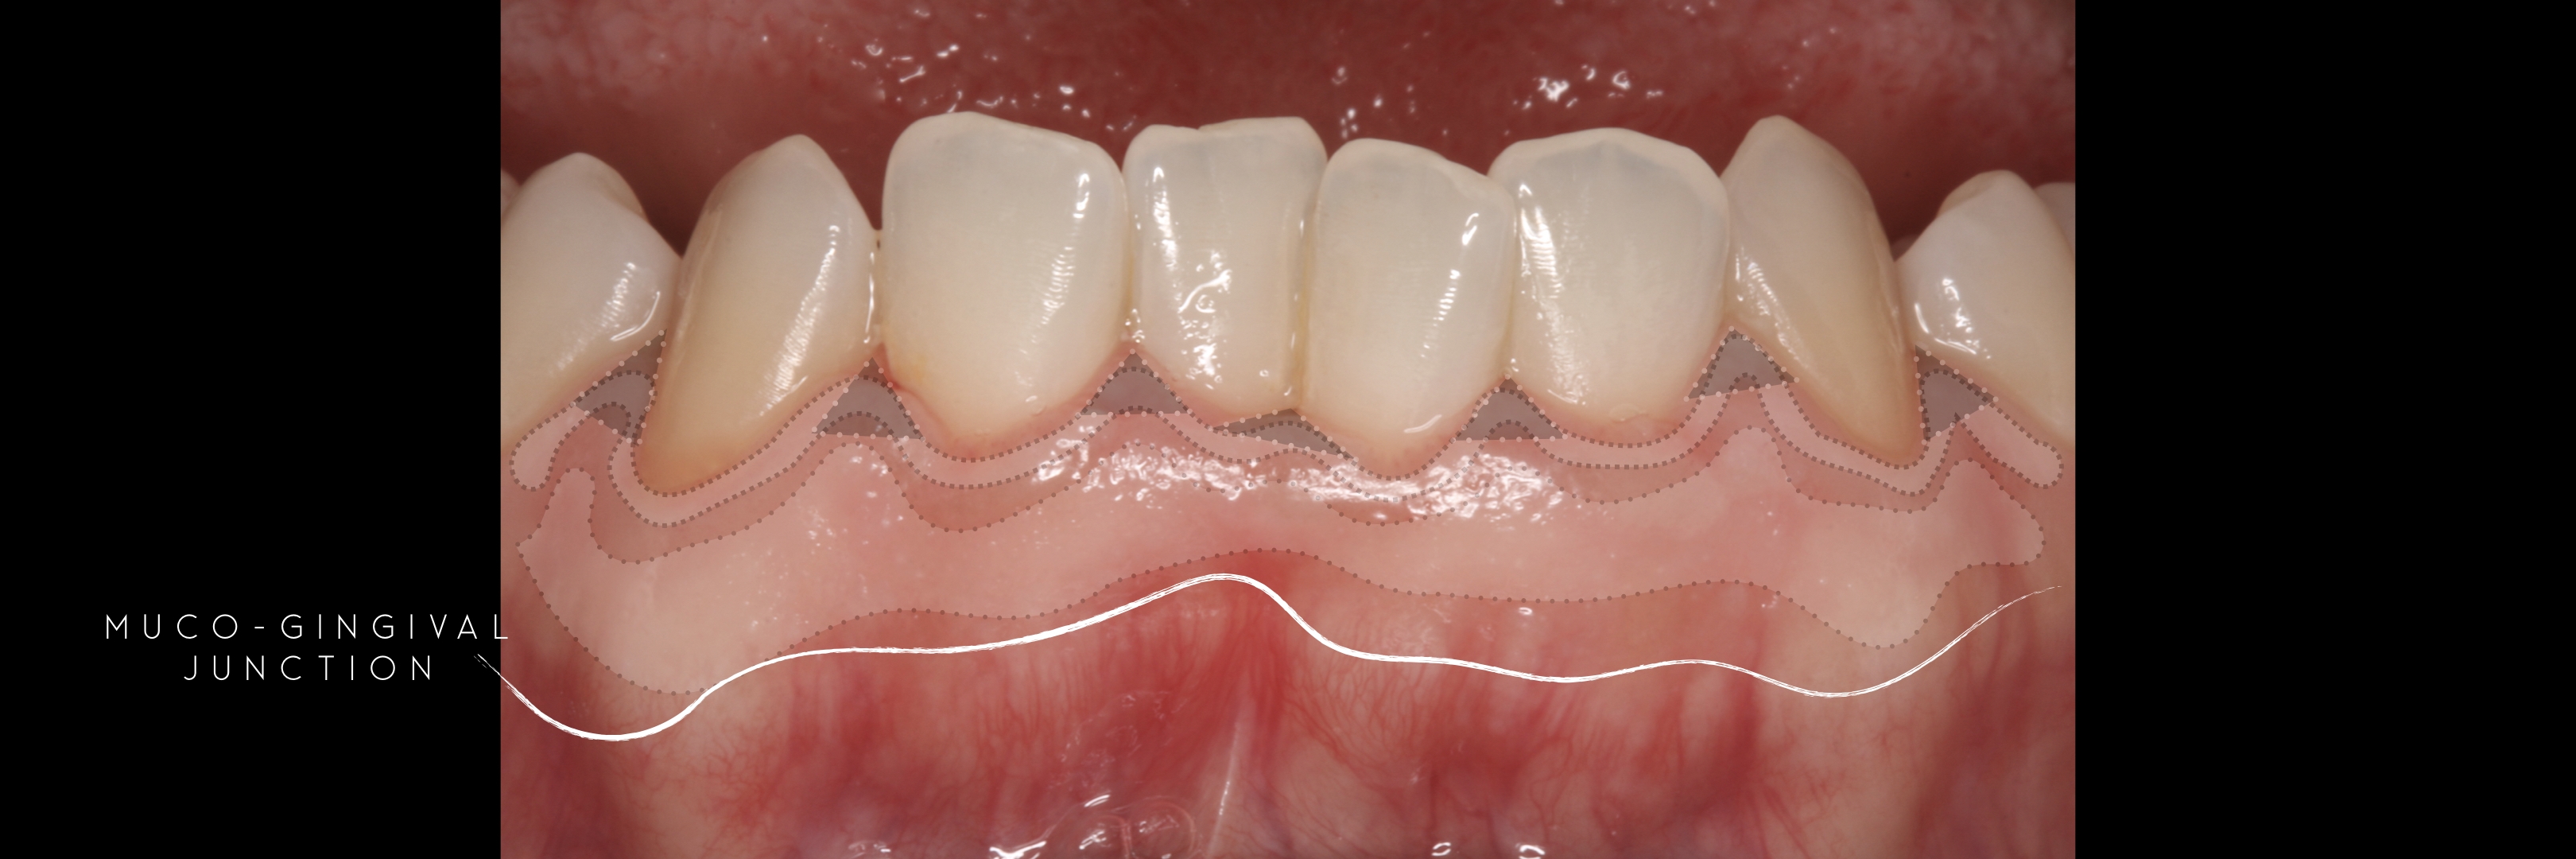

KERATINIZED gingiva includes

the free gingiva

(marginal gingiva & papillae)

and the attached gingiva extending from the gingival mar­gin to the mucogingival junction.

Generally we tend to forget about these 2 parameters, free and the attached gingiva are both essential parts of the keratinized gingiva.

This meaning that keratinized (load bearing capacity) is a mechanical characteristic that makes up for attached gingiva, providing it's immobility,  but also is of such importance as the thickness it provides around whatever perforates the epithelium, be it implants or teeth, being also keratinized (having load bearing capacity) at this location.

The width of the keratinized gingiva may vary between 1 and 9mm.

However, the question of how much gingiva is "adequate" has still not been investigated.

There was no answer at the time of Lang and Löe's paper -1972 - and still nowadays we still lack a final answer, but attached gingiva plays a major role on stable soft tissues around teeth and implants.